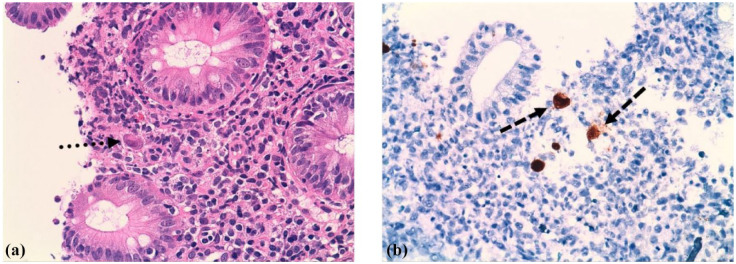

Dasatinib is a second-generation tyrosine kinase inhibitor employed for chronic myeloid leukemia (CML) treatment that achieves high rates of prolonged and complete molecular responses (MR). Among the adverse effects reported, it has been associated with hemorrhagic complications, mainly due to its inhibiting effects on platelet functions. In addition, immune alterations induced by dasatinib may elevate the risk of bleeding and cytomegalovirus (CMV) infection, particularly in the gastrointestinal tract, thus contributing to the development of hemorrhagic colitis. In this case report, we highlight three cases of CML receiving treatment with dasatinib where CMV hemorrhagic colitis occurred. All of them exhibited iron deficiency anemia as a premature clinical manifestation in the absence of intestinal symptoms, unlike cases previously reported in the literature. CMV infection was confirmed with stool samples or tissue quantitative polymerase chain reaction and/or immunohistochemistry staining in colon biopsies. All three cases could be managed with valganciclovir and iron supplements in an outpatient setting. Management strategies of dasatinib during and after CMV infection varied, as they are not yet established and need to be individualized based on the gravity of symptoms and disease state. Iron deficiency anemia during dasatinib treatment should raise suspicion for the potential presence of CMV colitis, prompting endoscopic studies to rule out this complication, even if intestinal symptoms are not present.